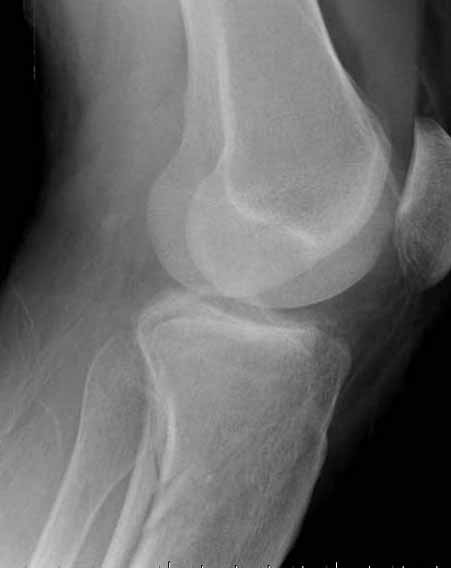

Двухколоннный перелом тибиал плато с вовлечением проксимального диафиза. Внутрисуставной компонент без смещения, и такой перелом можно лечить любым из описанных методов, о которых говорят наши коллеги.

Удобно аппаратом Илизарова или интрамедуллярным гвоздем. Гвозди не так сложно, как пугают, тем более Александр готов помощь с методичкой. Сперва надо установить компрессирующие шурупы на мыщелки. Давно отказались в пользу 3.5-4.0 мм кортикальных вместо толстых спонгиозных, потому что не доказаны преимущества толстых шурупов. Тонкие шурупы в субхондральной зоне смотрятся намного элегантнее, чем толстые 6.5.

Как понял, аппарат Илизарова не рассматривается предпочтительным для фиксации методом, хотя на фоне отека было бы идеальным для данного перелома. Для пластины требуется идеальная кожа, иначе наличие “суперсовременных имплантов” не поможет, и могут развиться серьезные осложнения.

Кстати, коллеги правы для уточнения характера перелома надо делать Компьютерную Томографию.